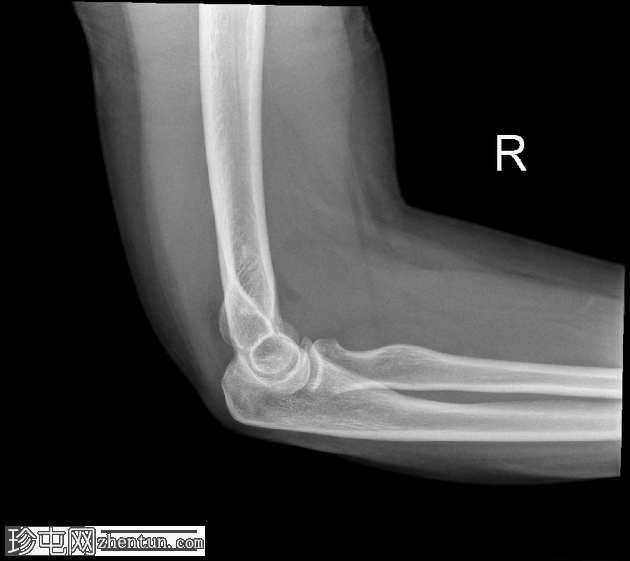

正位

侧位

侧位片显示前后脂肪垫征,提示关节囊扩张。

可见桡骨头轻微凹陷性骨折。

桡骨头骨折通常由肘关节伸直时手掌撑地摔倒所致。侧位X线片上前后脂肪垫征的存在是关节囊扩张(由关节积血和关节积液引起)的重要间接指标,即使皮质骨未见明显损伤,也是隐匿性骨折的标志